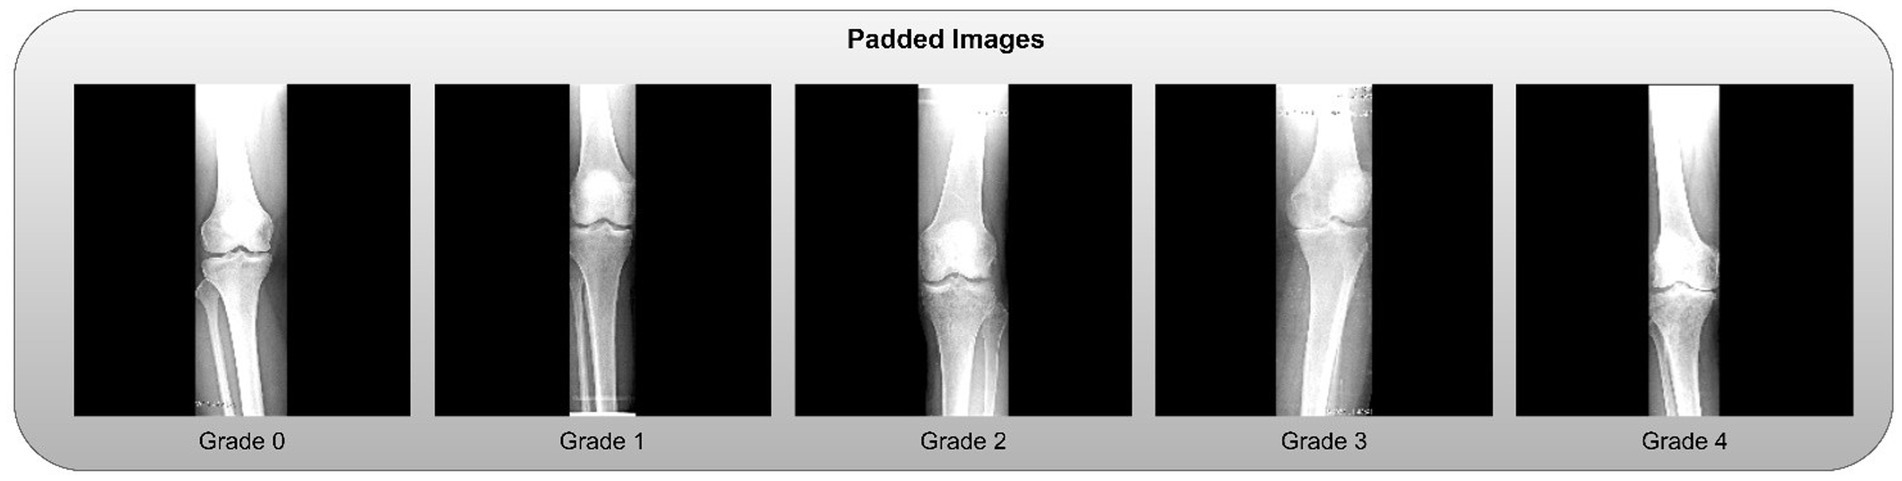

• Zero-Padding: To standardize dimensions without distorting the aspect ratio, zero-padding was applied to the sides of the cropped slices. Examples of the final padded knee slices are shown in Figure 4.

Figure 4

Series of X-ray images showing knee joints at different stages of degeneration, labeled Grade 0 to Grade 4. Each grade indicates increasing levels of joint damage, with Grade 0 showing a healthy knee and Grade 4 displaying severe degeneration.

Figure 4. Clipped knees with padded slices.